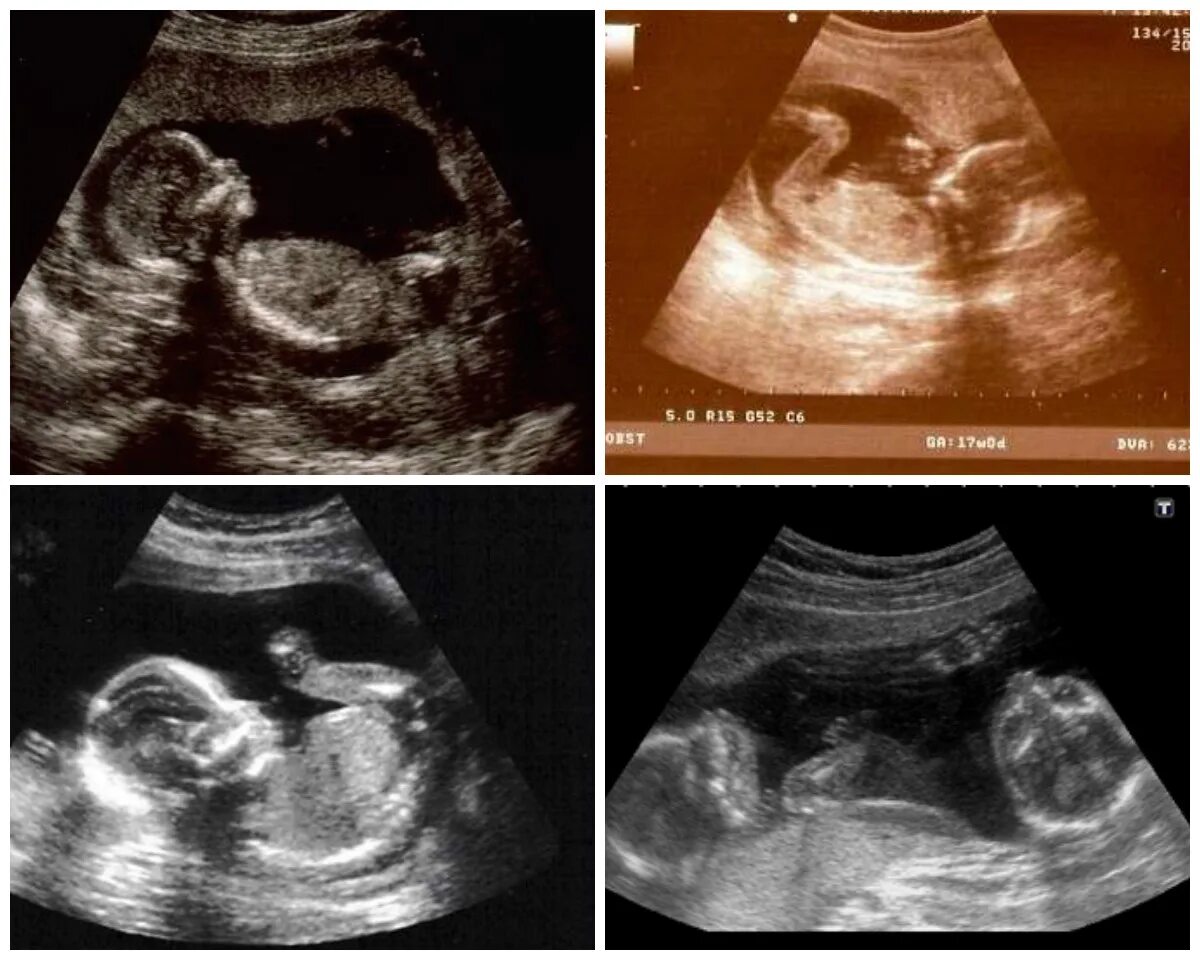

18 недель как выглядит малыш